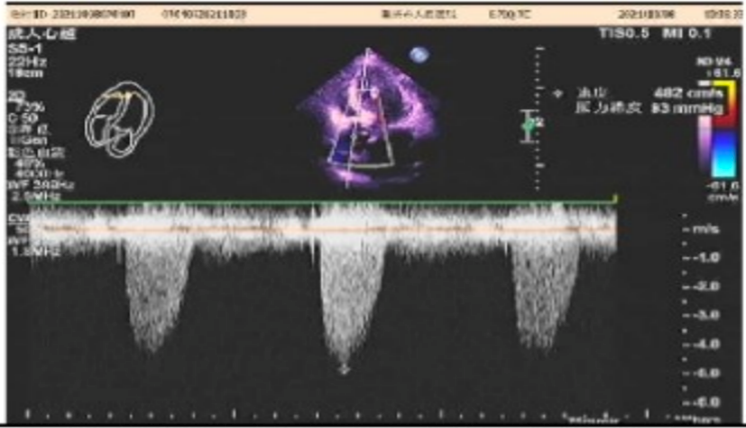

心脏彩超

左室射血分数EF值:58%;

左室舒张末期内径(LVD):55mm;

主动脉瓣大量返流,左房、左室增大;

并左室壁增厚;

二尖瓣、三尖瓣及肺动脉瓣少量返流;

左室舒张功能减退。